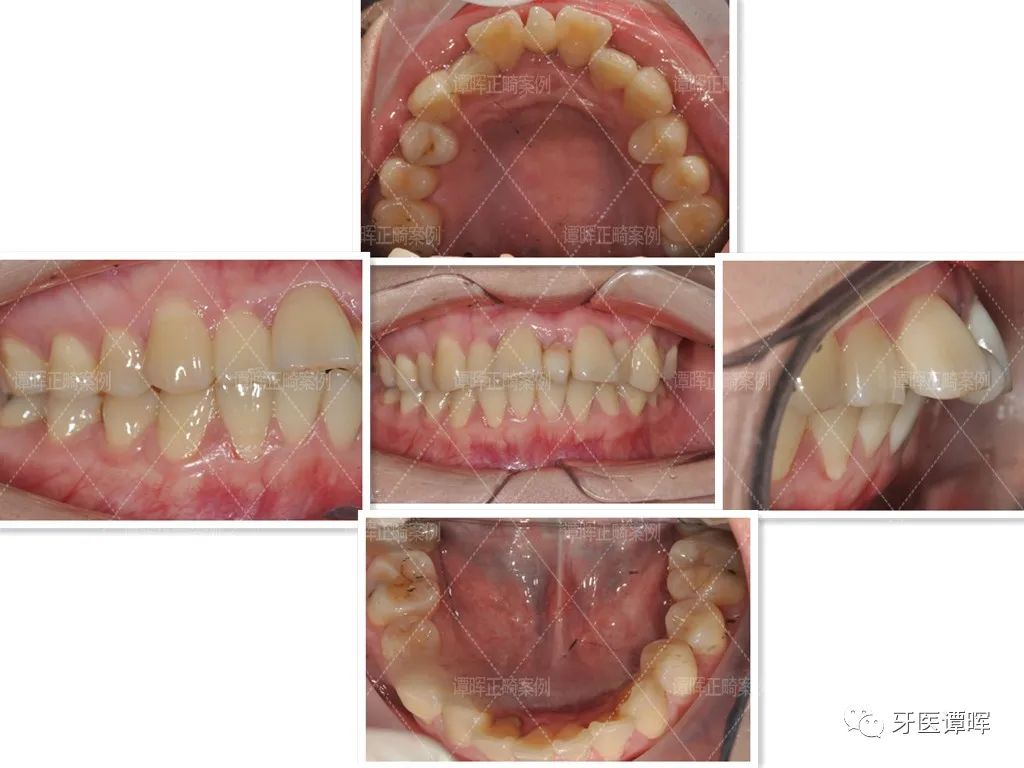

矫正前

△牙齿正面照:牙齿轻度扭转,一个门牙高一个门牙底,上前牙就看着就很不齐,微微张嘴时整体面部曲线不是很好,可以感觉到嘴凸。

△从口内照可以看出,上颌牙不齐,并未排齐在牙弓上。前牙往舌侧倾斜,牙齿也不对称。

△X线分析:明显看出前牙往前突,上牙的侧切牙也是非常不齐。